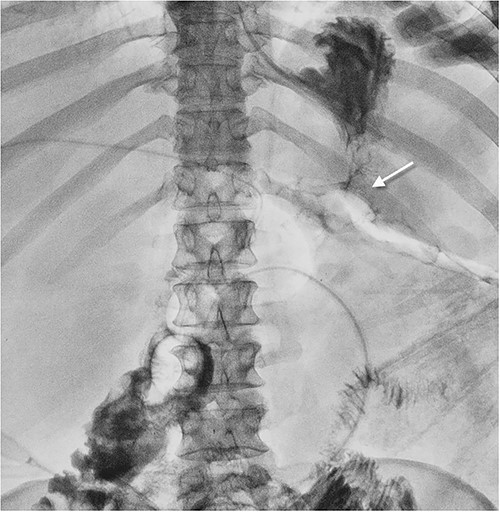

Fistulography with contrast was performed via sequential catheterization of all visually accessible fistulas (Fig. 3). Afferent and efferent small bowel loops, gastroenteric leakage, and previously formed enteroenteroanastomosis were identified.

Fistulogram showing gastroenteroanastomosis leakage. The contrast spilling from the gastroenteroanastomosis to the abdominal wall wound.